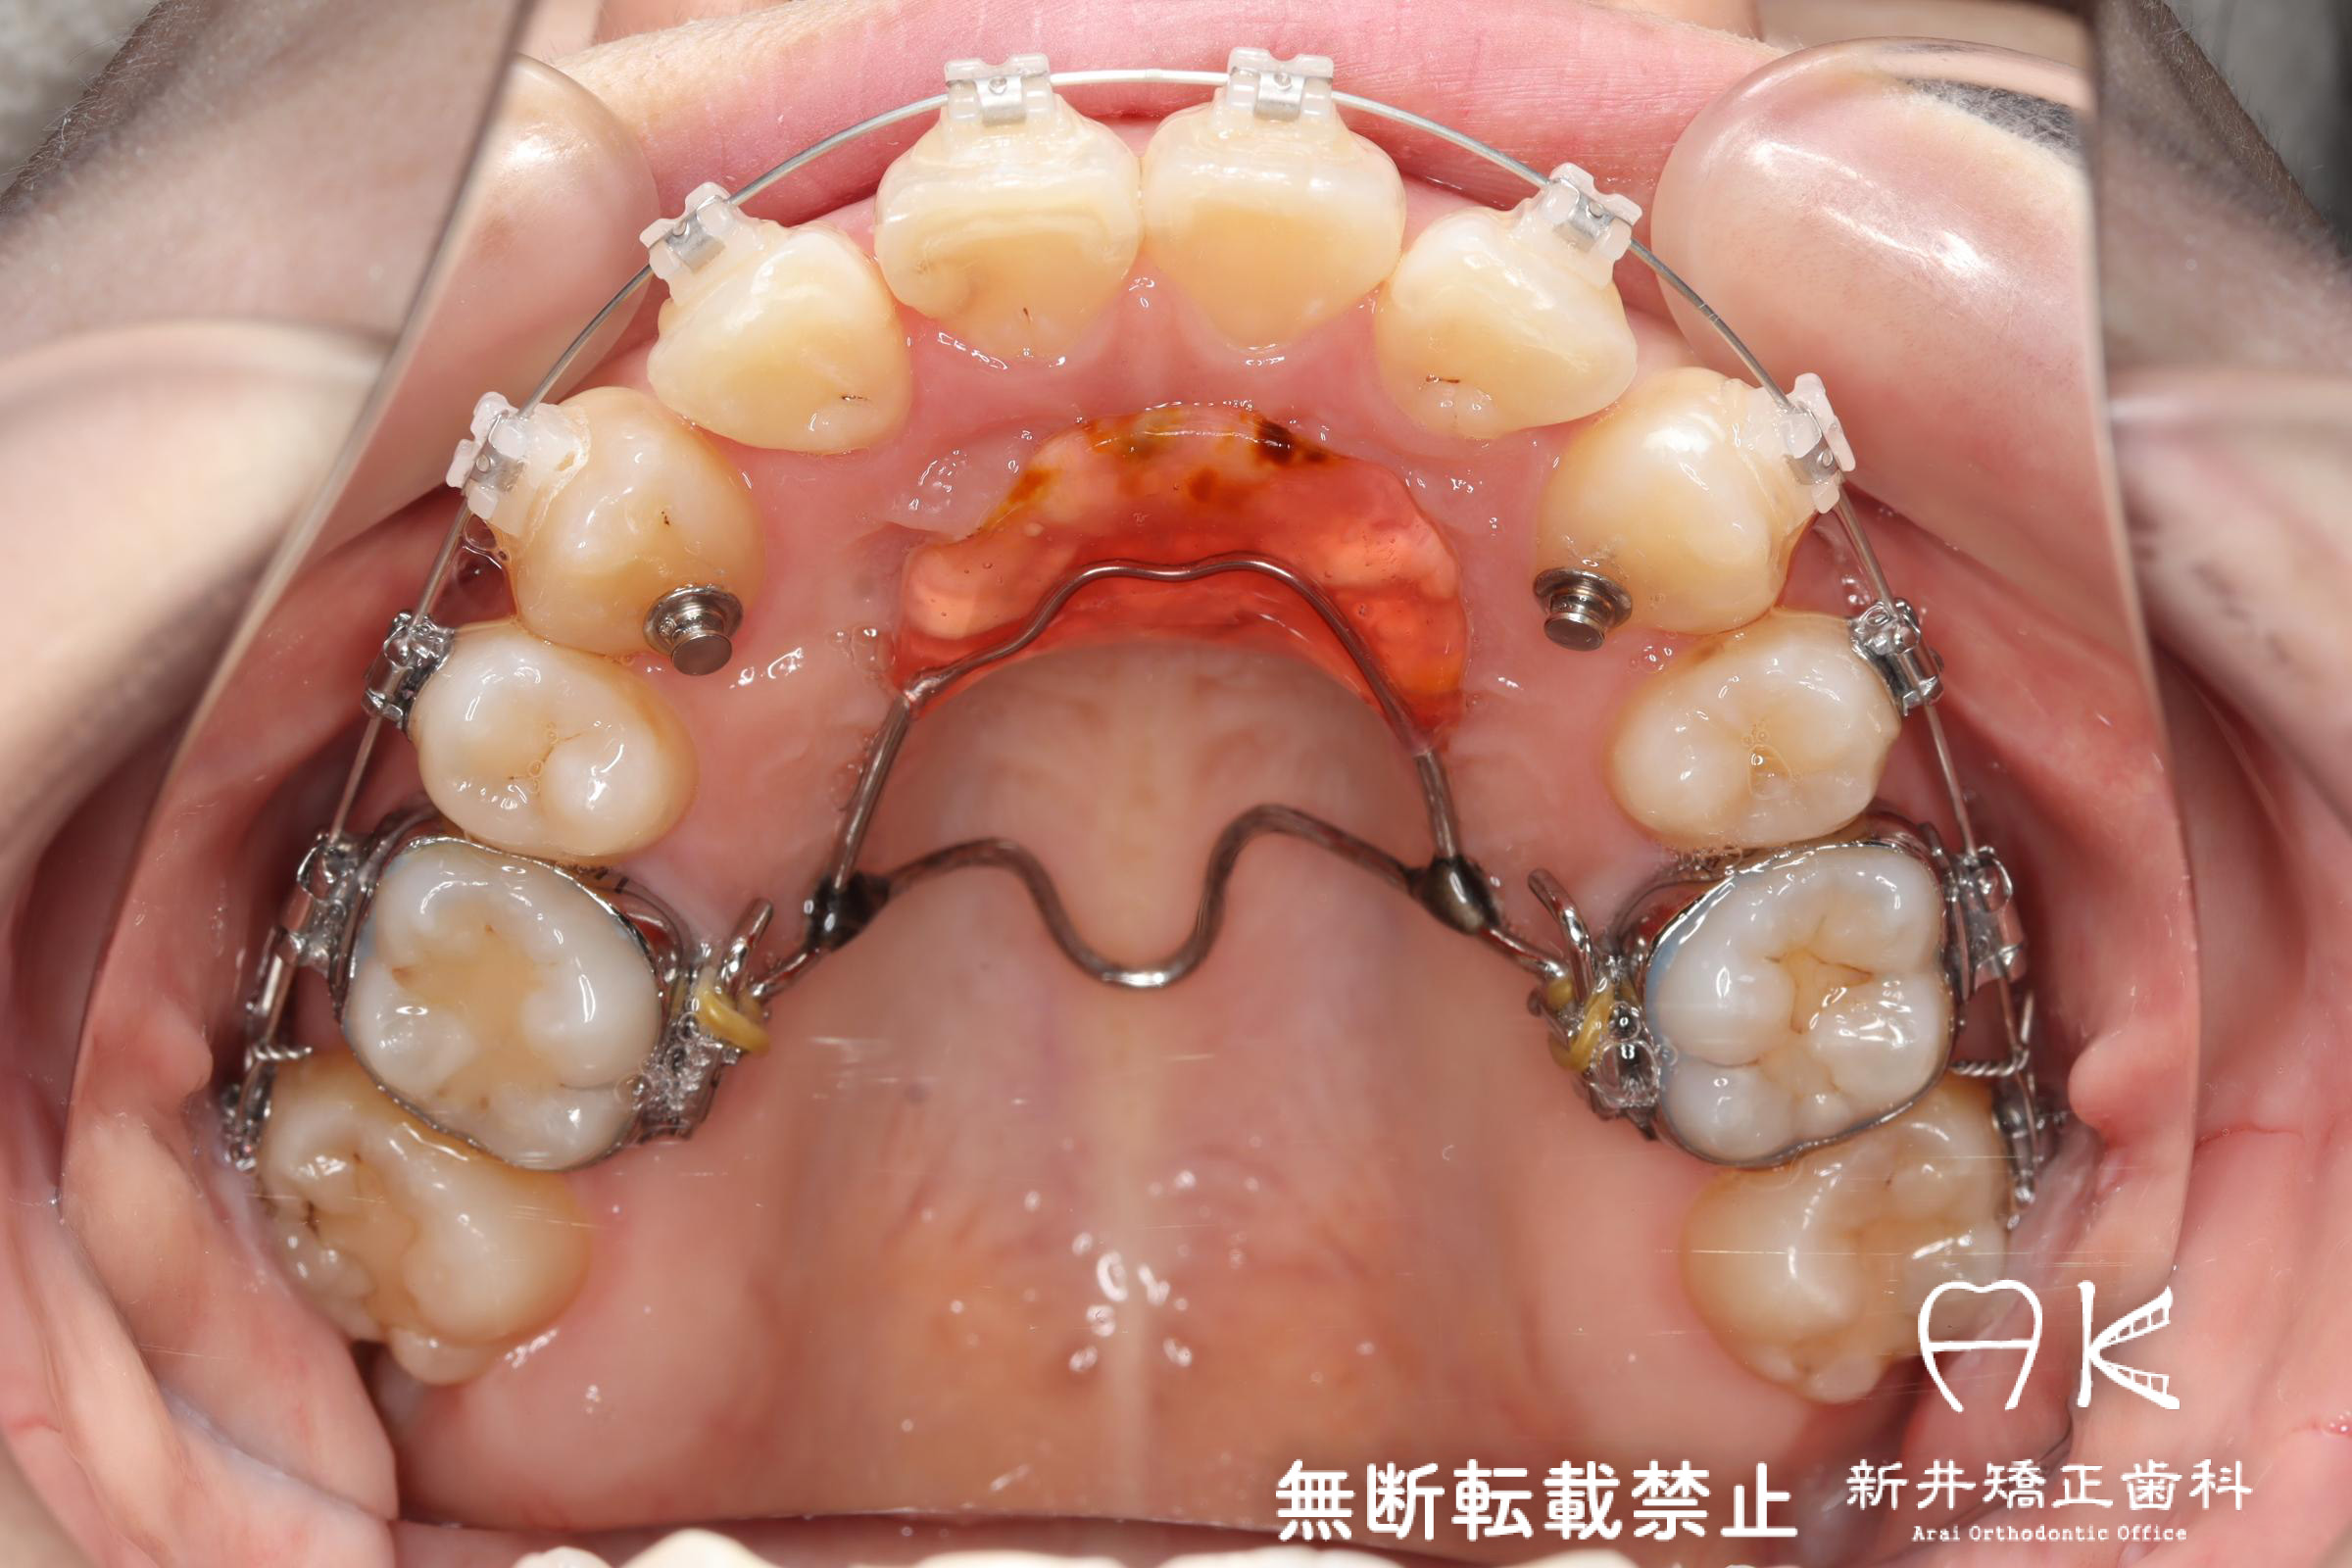

治療中

| 使用矯正装置 | 上顎:セルフライゲーションリンガルブラケット 下顎:セルフライゲーションブラケット(セラミッククリッピー) 歯科矯正用アンカースクリュー |